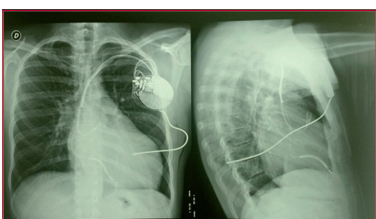

Altos umbrales de desfibrilación en un paciente con miocardiopatía hipertrófica con implante de catéter de desfibrilación subcutáneo